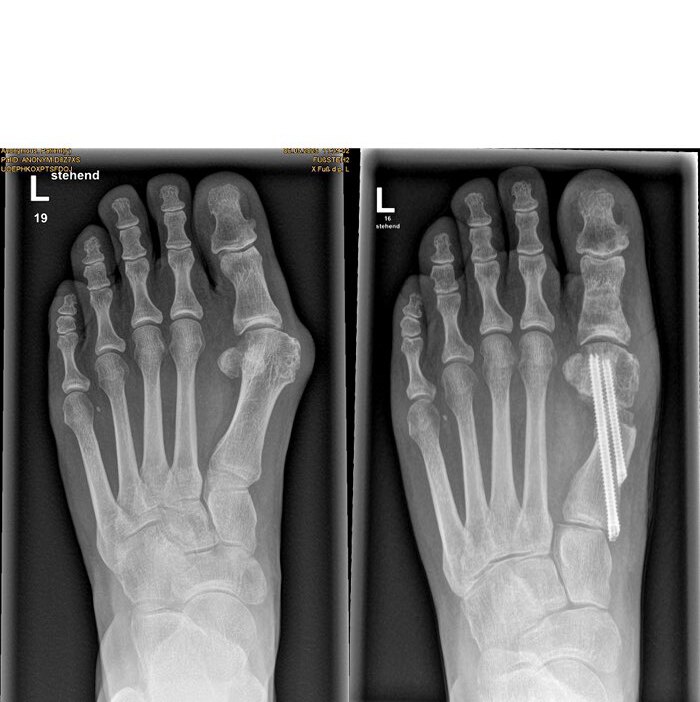

Es gibt unterschiedliche OP-Methoden zur Behandlung der Fehlstellung – von der Entfernung des Knochenvorsprungs über eine Umstellung des Mittelfußknochens bis hin zu einer Versteifungsoperation. Dr. Mann erklärt die neue Methode: »Mithilfe filigraner Werkzeuge, die wir durch vier millimeterkleine Schnitte einführen, durchtrennen wir den Mittelfußknochen unterhalb des Großzehengelenks. Wir verschieben das Köpfchen zur Mitte und fixieren es mit zwei speziell für dieses Verfahren hergestellten, abgeschrägten Schrauben. Abschließend wird der überstehende Knochen außen entfernt.« All dies geschieht unter Röntgensicht. Die Vorteile der sogenannten MICA-Methode (Minimalinvasive Chevron-/Akin-Osteotomie): »Man muss das Gelenk nicht öffnen, benötigt keine größeren Hautschnitte und die Rehabilitationszeit ist viel geringer als nach einer herkömmlichen OP. Gleichzeitig gibt es weniger Schmerzen, Narben und Wundheilungsprobleme«, so der Facharzt. Ute Pacher erhält nach der OP zunächst einen Spezialschuh – ihren Fuß darf sie gleich wieder belasten. Sechs Wochen später trägt sie bereits wieder ihre eigenen Schuhe.